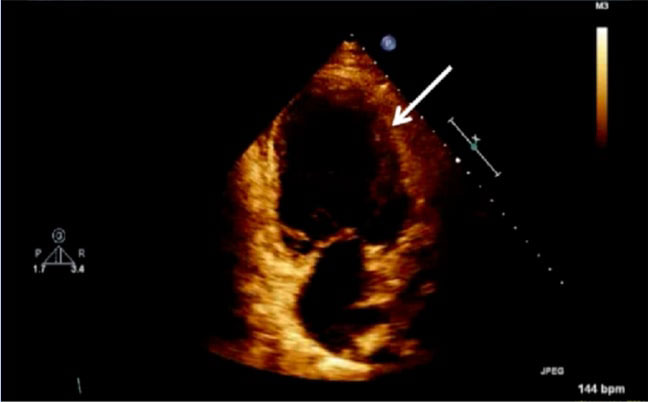

The exemption from the Institutional Review Board of Cleveland Clinic and consent from the patient were obtained for our case. A 42-year-old obese (body mass index 37.6 kg/m2) female at 38w2d, G2P1 with past medical history significant for gestational diabetes mellitus, presented with a three-day history of shortness of breath, orthopnea, chest tightness, tachycardia, headache, and swollen feet. She denied fever, vision changes, and right upper abdominal pain. No history of cardiac diseases or chronic hypertension was reported. Her vital signs included blood pressure (BP) of 145/98 mmHg, respiratory rate of 30 breaths per minute, heart rate of 150 beats per minute (bpm), and blood oxygen saturation (SpO2) of 98% on 10 liters per minute of oxygen through a non-rebreather mask. She was afebrile. Physical exam revealed loud S3 gallop, bilateral basilar rhonchi, and bilateral feet and ankle edema. Fetal monitoring was normal with a heart rate of 125 bpm. Laboratory results showed a white blood cell count of 12.8 k/µL, urine protein of 74 mg/dl, NT-proBNP of 1017 pg/ml, mildly elevated aspartate transaminase of 45 U/L and alanine transaminase of 30 U/L, and normal troponin. Electrocardiogram reported sinus tachycardia with borderline LV hypertrophy and frequent premature ventricular contractions (PVCs). Chest X-ray showed bilateral basilar infiltration. Echocardiogram revealed dilated LV with severely decreased function, EF of 25%, diffuse LV hypokinesia, and normal right ventricle function (Figure 1 and Figure 2). The patient started contractions and labor analgesia was administered through the epidural catheter; BP was noted to be 118/62 mmHg. Coagulation profile was normal. She was admitted to the intensive care unit (ICU) and Swan Ganz catheter, central, and arterial lines were inserted to monitor hemodynamics and heart function. Although our patient's clinical symptoms may lead us to consider preeclampsia, we ruled out preeclampsia because her labs did not meet criteria for diagnosis. Our patient was diagnosed with PPCM, for which she was placed on intravenous (IV) furosemide, tocolytic medication, and digoxin. Tocolytic medication was given to delay delivery until heart function improved, as the patient was unable to lie flat and EF was very low.

Figure 1: Echocardiogram of apical four chamber view of the heart showing dilated left ventricle and reduced ejection fraction; LV: left ventricle, EF: ejection fraction, A4C: apical four chamber, Vol: volume.